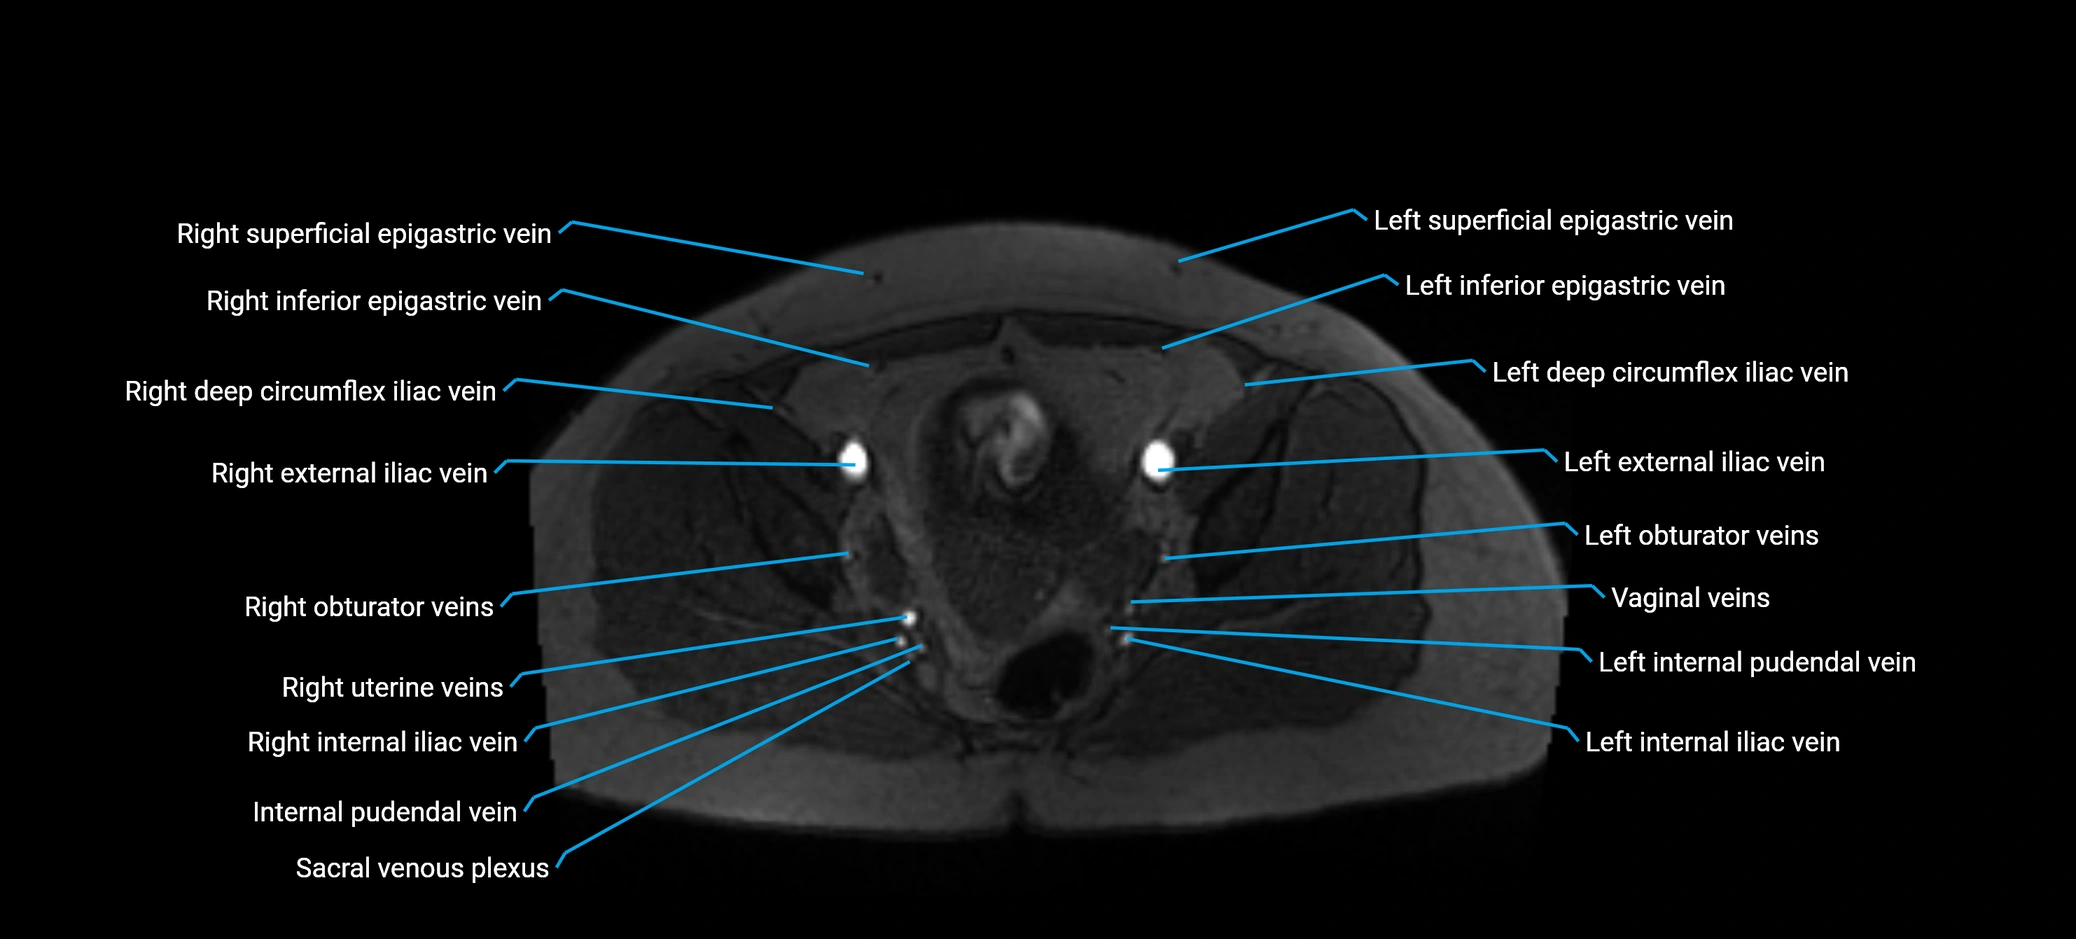

The anterior right branch of the portal vein is a major intrahepatic division of the right portal vein. After the main portal vein bifurcates into right and left branches, the right portal vein divides into anterior and posterior segmental branches.

The anterior right branch supplies the anterolateral liver segments (Segment V) and anteromedial liver segments (Segment VIII) within the right hepatic lobe. It operates as a key vascular route delivering nutrient-rich portal venous blood to the central and superior right liver.

This segmental vasculature is of major importance in hepatic surgery, embolization, segmental resection, transplantation, and imaging-based liver segmentation.